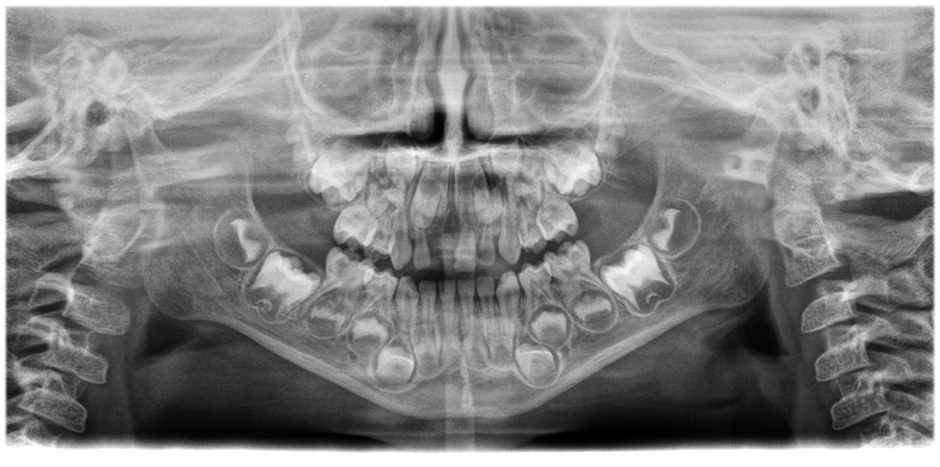

• Panorama images of outstanding clarity and definition

with the innovative 21-layer autofocus system seamlessly integrated with a patient positioning correction.

Move the slider to see the difference (left image without, right image with autofocus and patient positioning correction)